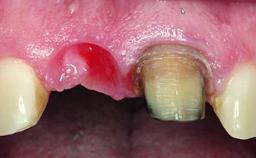

A 49-year-old female patient was referred for implant therapy to replace the upper right central incisor (tooth 11). The tooth had been assessed by an endodontist who diagnosed a vertical fracture of the root. The tooth had a hopeless prognosis and needed to be extracted. The patient was healthy and was not taking any medications. She was allergic to penicillin. The patient had high esthetic demands but her expectations were realistic. The extraoral examination revealed no facial asymmetries. The right temporomandibular joint demonstrated an opening click but was otherwise asymptomatic. The lip line was high with a significant gingival display.